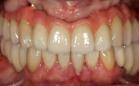

En la radiografía panorámica, podemos observar 28 dientes presentes con los terceros molares en formacion así como el correcto paralelismo de todas las piezas dentales, (Figura 10).

Resultados

El tiempo total del tratamiento fue de 2 años y 6 meses, la corrección del apiñamiento maxilar y mandibular, el overbite y el overjet, la incorporacion del sector anteroinferior al arco. Se obtuvo una clase I canina y una clase I molar bilateral. La corrección de las líneas medias del paciente. Se indicaron los retenedores Hawley superior e inferior (Figura 11).

Figura 8. Extraoral e intraoral de frente. Figura 9. Intraoral derecha e izquierda. Figura 10. Radiografía panorámica final. Figura 11. Comparación de inicio, progreso, final extraoral e intraoral.